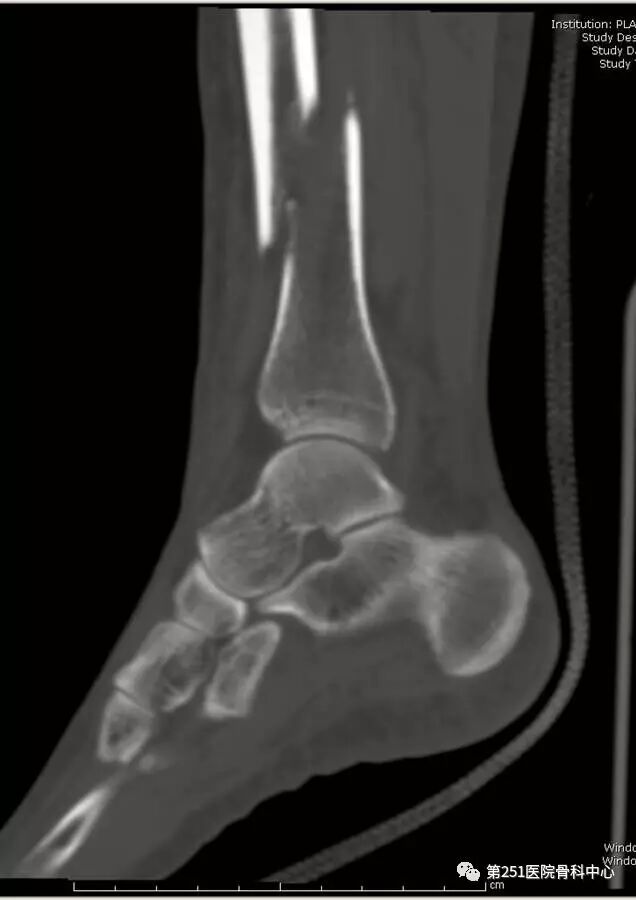

病例1:男性,40岁,车祸伤,胫腓骨多段骨折。

![]()